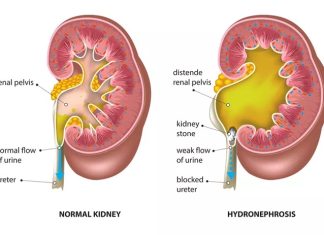

Hẹp Khúc Nối Bể Thận – Niệu Quản (UPJO) Theo Từng Nhóm Tuổi

Bài viết cung cấp cái nhìn toàn diện về bệnh lý hẹp khúc nối bể thận – niệu quản (Ureteropelvic Junction Obstruction – UPJO), phân tích sự khác biệt về sinh lý bệnh, chẩn đoán và điều trị từ trẻ sơ sinh đến người cao tuổi dựa trên các hướng dẫn quốc tế (EAU, AUA, ESPU).

Hẹp Khúc Nối Bể Thận – Niệu Quản (UPJO) Theo Từng...

Bài viết cung cấp cái nhìn toàn diện về bệnh lý hẹp khúc nối bể thận – niệu quản (Ureteropelvic Junction Obstruction – UPJO), phân tích sự khác biệt về sinh lý bệnh, chẩn đoán và điều trị từ trẻ sơ sinh đến người cao tuổi dựa trên các hướng dẫn quốc tế (EAU, AUA, ESPU).